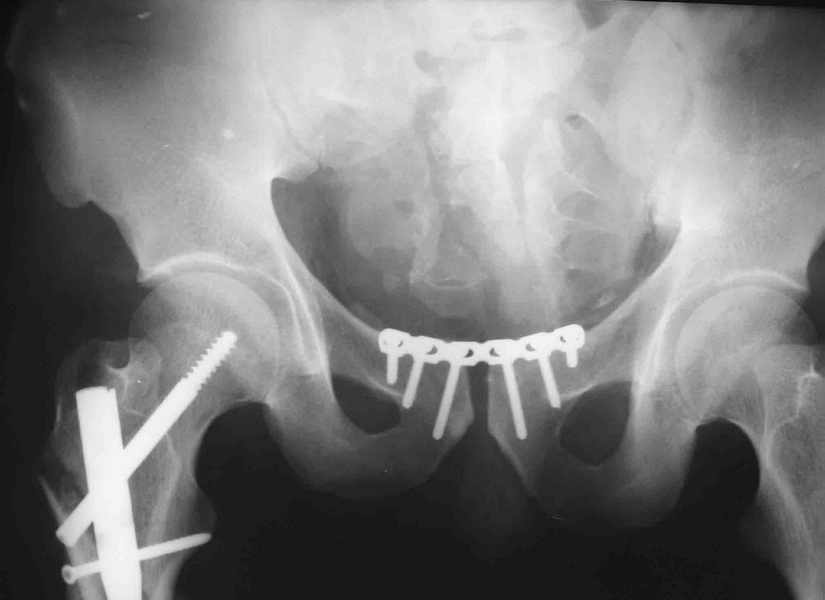

извините за опоздание , вот фотографии

Репозиция действительно очень неплохая, но чтобы уменьшить риск развития поздней нестабильности, в такой ситуации лучше выполнить синтез лонного сочленения пластиной и оставить аппарат месяца на 2.

В представленном случае повреждение несомненно ротационное и реальный диастаз как раз около пограничных 2,5 см, репозиция идеальная, достигнута в первые дни после травмы. Я бы ограничился 3 мес фиксации в аппарате с ограничением нагрузки первый месяц, и функциональными снимками в 6 -8 недель.

ПЕРЕСМАТРИВАЛ РАЗНЫЕ СНИМКИ И НАШЕЛ НА ЭТУ ТЕМУ ФОРУМА СНИМОК. БОЛЬНОЙ БЫЛ ПРООПЕРИРОВАН НА ПРАВОЕ БЕДРО ПОСЛЕ ЧЕГО СДЕЛАН ТАЗ В ЦЕЛОМ. ВОТ ЧТО НАШЛОСЬ.

КАКОЕ ВАШЕ МНЕНИЕ О ТАКТИКЕ.

ДУМАЮ ПРОШЛО ОКОЛО 10 ДНЕЙ.

Вот вариант решения похожей ситуации